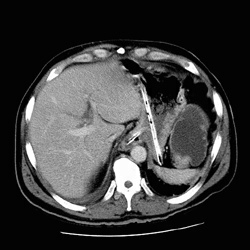

RADIOLOGY: GASTROINTESTINAL: GI: Case# 126: OBSTRUCTING COLON CA. 68-year-old male with bowel obstruction identified on plain films of the abdomen. The patient has worsening abdominal distention. 1. There is a high-grade colonic obstruction at the level of the splenic flexure. There is suggestion of a small soft tissue mass in this area. 2. There is a small right pleural effusion with some atelectasis in the right lower lobe. 3. The primary service was notified of the results immediately following the examination.